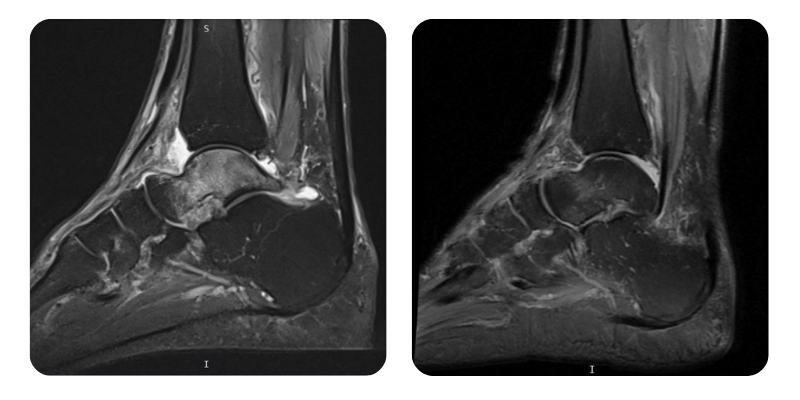

Before

After

Anamnesis: Three months ago, the patient suffered a fracture of the distal right fibular epiphysis, treated with cast immobilization. One month later, he experienced an ankle sprain followed by persistent ankle pain. MRI revealed aseptic necrosis of the talus. Past medical history includes hypertension treated with Preductal and prostate adenoma.

Diagnosis: Avascular necrosis of the right talus.

Evolution: Edema has decreased by approximately 90%.